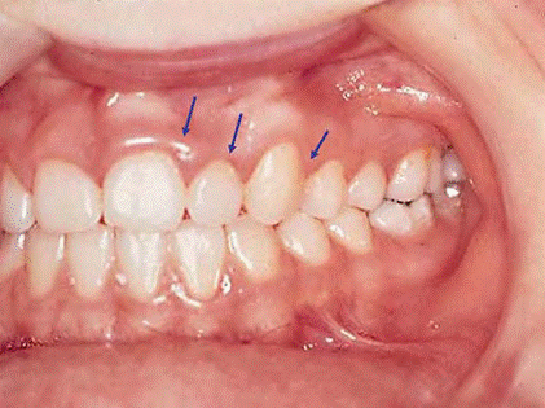

Diş Eti İltihabı Nedir?Diş eti iltihabı, diş etlerinin enfeksiyonu veya iltihaplanması durumudur. Genellikle dişlerin etrafındaki yumuşak dokularda meydana gelir ve periodontal hastalıkların başlangıç aşaması olarak kabul edilir. Diş eti iltihabının temel nedeni, dişlerdeki plak birikimi ve buna bağlı olarak bakteriyel enfeksiyonlardır. Diş Eti İltihabının Belirtileri Diş eti iltihabının belirtileri, genellikle hafif düzeyde başlar ve zamanla şiddetlenebilir. Belirtiler şunlardır: